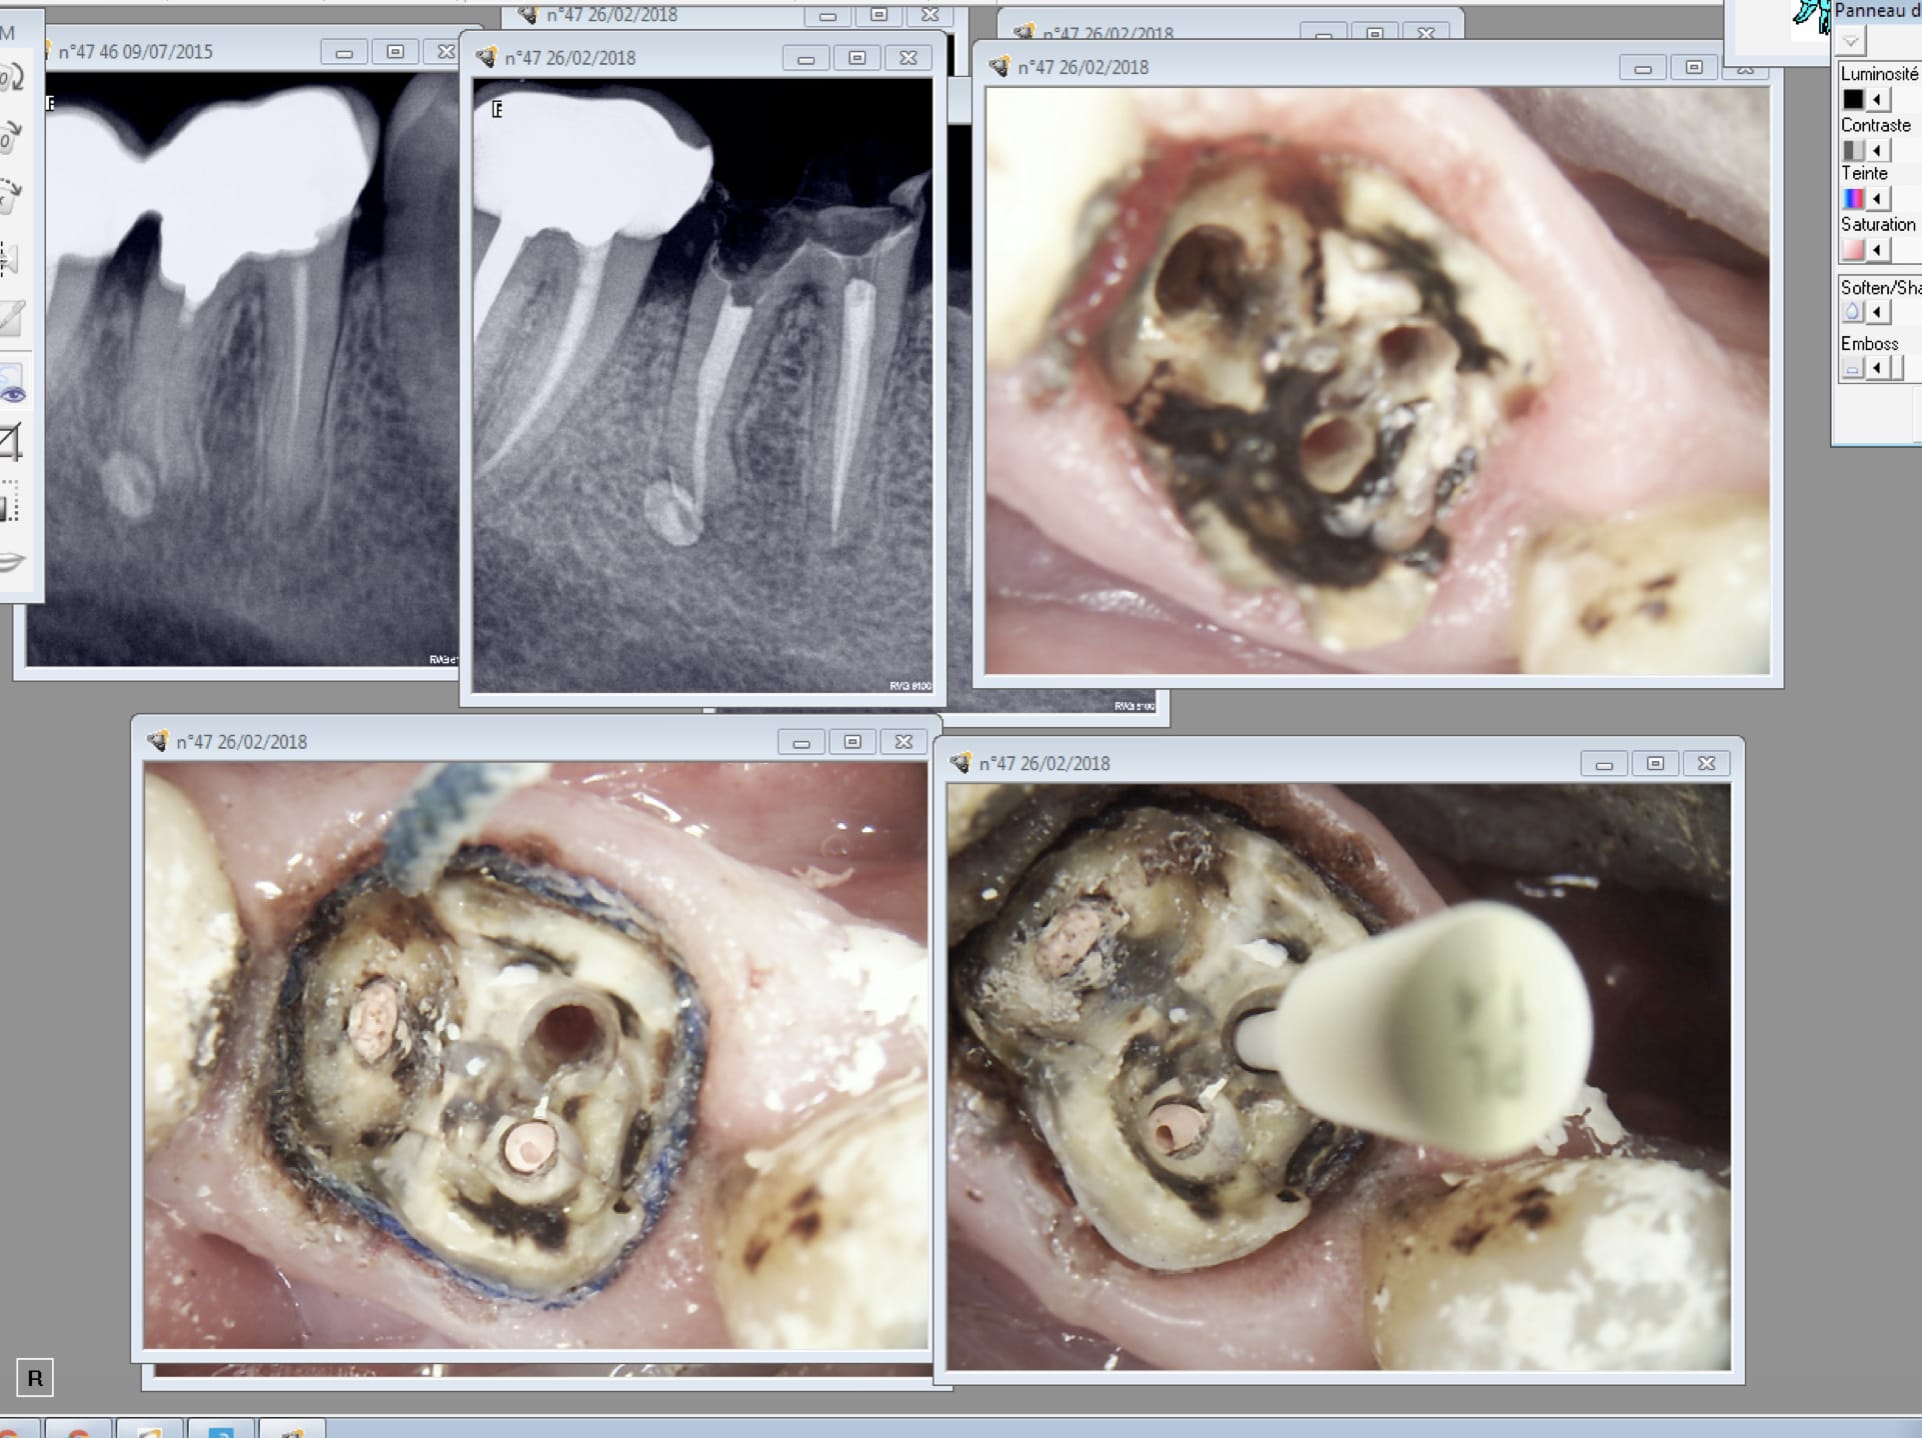

L'autre est pas Top. Trop pressé de faire l'empreinte et toute mon attention a été captée pour trouver les limites en distal. 4 mm sous gingival. Après un . RTE sportif + dépose couronne soudée ( j'ai re scellé la 47)

Là tu te dis ca va saigner ! -))) Donc tu recrées un sillon gingival au laser + double fil.

Première empreinte......

Tiens ? Un micro trou dans le composite du moignon. Je l'avais pas vu meme avec des loupes. -))))